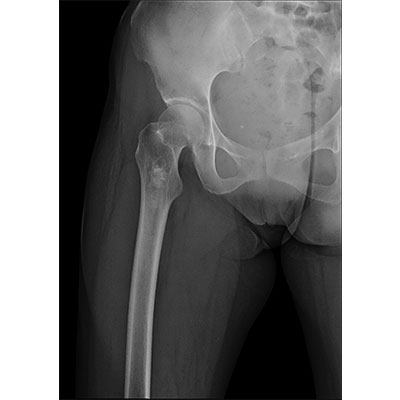

● 采用自主研發(fā)的技術,在保證優(yōu)質圖像的前提下,大大降低X射線劑量,用心呵護醫(yī)護工作者及患者的健康。

● 短曝光時間,便于老年人、兒童、殘疾人進行臨床拍攝。避免這類群體因不能有效控制身體運動等因素造成的運動偽影,提高攝片質量及效率。